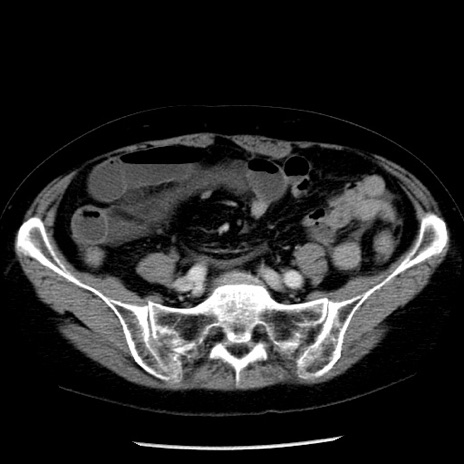

症例13(横断像)

【症例】70歳代女性

【主訴】腹痛、嘔吐

【現病歴】15時間程前(昨晩)より腹痛あり。今朝になっても症状の改善なく、嘔吐あり。腹痛も増悪あり、救急外来受診。

【既往歴】子宮癌全摘術後

【身体所見】意識清明、BP 121/72mmHg、P 74bpm、SpO2 100%(RA)、腹部:平坦・軟、腸雑音ほぼ聴取せず。下腹部・心窩部・臍左上に圧痛あり。反跳痛なし。

【データ】WBC 10600、CRP 0.15